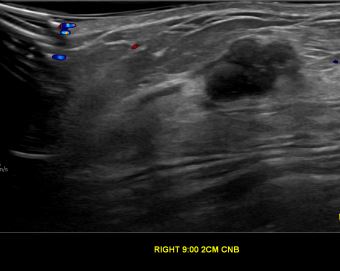

상기환자는 우측 유방 유두분비물 있어 내원하신 40대 후반

여성분으로 의심스러운 우측유방혹 조직검사 시행해 제자리암으로 진단되었습니다